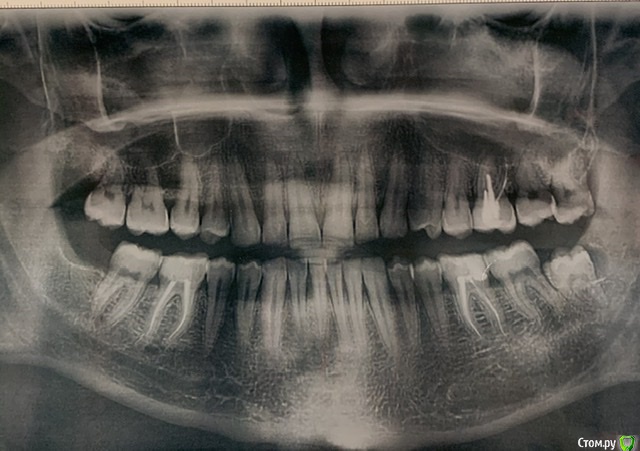

strelokvlz Опубликовано 4 августа, 2020 Поделиться Опубликовано 4 августа, 2020 (изменено) Здравствуйте. 17 июля нагноилась полностью скрытая под десной левая нижняя восьмёрка. Обратился в частную клинику где произвели разрез десны чтобы освободить зуб. Все промыли, назначили антибиотики Ципролет 5 дней и отправили на ОПТГ. Сказали что зуб сложный, удалять не возьмутся и направили в городскую стоматологию. Сделал снимки и пошёл на приём в поликлинику. К слову она неплохая, врачи хорошие. Хирург посмотрел снимок, сказал что есть полость(киста?) на зубе и назначил дату удаления. 24 июля зуб удалили. Резали десну, пилили, но в целом все прошло минут за 20. Десну зашили, поставили дренаж. Выписали амоксицилин 5 дней, антигистаминное, лёд. Повторный приём через 3 дня. Отека не было, боль умеренная в течение двух дней. На следующий день после операции вылетел дренаж во время еды, а ещё через день полностью разошлись швы и появилась боль в десне. На следующий день поехал на приём. Врач осмотрел лунку и сказал что в принципе ничего страшного что швы разошлись, равна большая и мол иногда, но бывает. Промыл антисептиком и плотно уложил альвожель в рану, повторно зашивать не стал. Сказал приезжать через день для замены лекарства. Начиная со следующего дня появилась постоянная ноющая боль и сильное реагирование соседней 7ки на холодное. Ездил 4 раза на замену лекарства и осмотр. Пожаловался на боль, после чего отправили на рентген. По снимку врач сказал что из за травмы оголилась шейка соседнего зуба и предложил либо потерпеть до зарастания Десны либо депульпировать. Но так как семерка здоровая, от депульпации я отказался. Опять заложили альвожель и отправили домой, на повторный приём только через 5 дней. В итоге на 11 день после операции присутствует постоянная ноющая боль в районе лунке, не очень приятный запах, переодически слюна имеет кисло сладкий привкус (гной?) и сильная чувствительность в районе лунки (корень семерки?). Так и должно быть? Или стоит волноваться? Врачу я вроде бы доверяю и с его слов ему нравится как проходит заживление, но я уже устал от постоянной ноющей боли и запаха. Зарастёт ли шейка семерки или лучше все таки согласиться на депульпацию? Снимки оптг до операции и после прикрепляю. Изменено 4 августа, 2020 пользователем strelokvlz Ссылка на комментарий